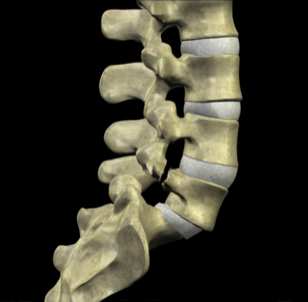

To understand how both mechanisms cause slippage, it is important to understand the anatomy of the vertebral motion segment. Each level of your spine functions as a three-joint complex. There are two facet joints in the back and a large disc that acts as a joint in front. This tripod creates great stability, supports the weight above each level and provides support for movement in all directions. As long as the disc remains healthy, it can withstand these forces for many years without any symptoms.

The pars functions as a bony hook and when fractured the posterior support for the vertebrae is broken. It can cause a forward slippage with time.

Many people with spondylolysis do not have problems for many years as their disc continues to be healthy. With a stress fracture, there is decreased posterior support in the vertebral segment causing more forces to be placed on the disc in front. This can cause degenerative disc disease, where the disc progressively breaks down and does not adequately support the bone above. Disc degeneration causes supporting collagen fibers in the disc to breakdown, allowing the disc to lose water. When it begins to dehydrate, it loses height and function. As the disc narrows, the bones above and below the disc can move or slip on each other. In addition, it is possible for the fracture gap at the pars to widen, causing the vertebra to shifts forward. This forward slippage is called spondylolisthesis. Imagine a tripod stool where two back legs have been partially cut through. With time and movement, the stool would be unstable and tip forward. There is not supposed to be any movement of these bones. This movement indicates segmental spinal instability.